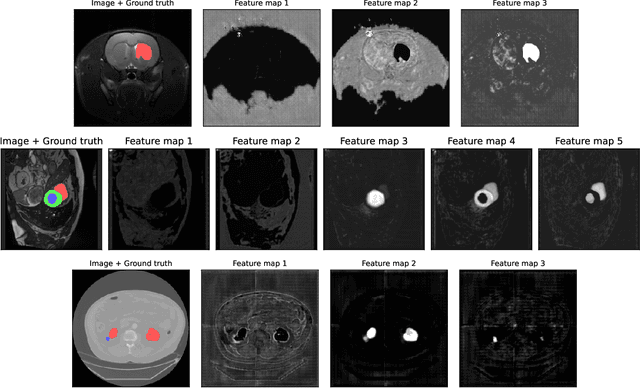

Abstract:We present Sauron, a filter pruning method that eliminates redundant feature maps by discarding the corresponding filters with automatically-adjusted layer-specific thresholds. Furthermore, Sauron minimizes a regularization term that, as we show with various metrics, promotes the formation of feature maps clusters. In contrast to most filter pruning methods, Sauron is single-phase, similarly to typical neural network optimization, requiring fewer hyperparameters and design decisions. Additionally, unlike other cluster-based approaches, our method does not require pre-selecting the number of clusters, which is non-trivial to determine and varies across layers. We evaluated Sauron and three state-of-the-art filter pruning methods on three medical image segmentation tasks. This is an area where filter pruning has received little attention and where it can help building efficient models for medical grade computers that cannot use cloud services due to privacy considerations. Sauron achieved models with higher performance and pruning rate than the competing pruning methods. Additionally, since Sauron removes filters during training, its optimization accelerated over time. Finally, we show that the feature maps of a Sauron-pruned model were highly interpretable. The Sauron code is publicly available at https://github.com/jmlipman/SauronUNet.

Abstract:Segmentation of rodent brain lesions on magnetic resonance images (MRIs) is a time-consuming task with high inter- and intra-operator variability due to its subjective nature. We present a three-dimensional fully convolutional neural network (ConvNet) named RatLesNetv2 for segmenting rodent brain lesions. We compare its performance with other ConvNets on an unusually large and heterogeneous data set composed by 916 T2-weighted rat brain scans at nine different lesion stages. RatLesNetv2 obtained similar to higher Dice coefficients than the other ConvNets and it produced much more realistic and compact segmentations with notably less holes and lower Hausdorff distance. RatLesNetv2-derived segmentations also exceeded inter-rater agreement Dice coefficients. Additionally, we show that training on disparate ground truths leads to significantly different segmentations, and we study RatLesNetv2 generalization capability when optimizing for training sets of different sizes. RatLesNetv2 is publicly available at https://github.com/jmlipman/RatLesNetv2.